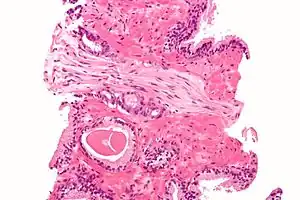

Each axon is surrounded by a layer of connective tissue called the endoneurium. The axons are bundled together into groups called fascicles, and each fascicle is wrapped in a layer of connective tissue called the perineurium. The entire nerve is wrapped in a layer of connective tissue called the epineurium. Nerve cells (often called neurons) are further classified as either sensory or motor.

Each nerve is covered on the outside by a dense sheath of connective tissue, the epineurium. Beneath this is a layer of fat cells, the perineurium, which forms a complete sleeve around a bundle of axons. Perineurial septae extend into the nerve and subdivide it into several bundles of fibres. Surrounding each such fibre is the endoneurium. This forms an unbroken tube from the surface of the spinal cord to the level where the axon synapses with its muscle fibres, or ends in sensory receptors. The endoneurium consists of an inner sleeve of material called the glycocalyx and an outer delicate meshwork of collagen fibres.[2] Nerves are bundled and often travel along with blood vessels, since the neurons of a nerve have fairly high energy requirements.